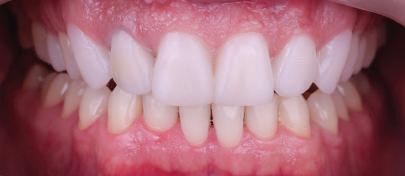

планта бе поставена временна коронка (фиг. 10 и 11), докато бъде изготвена окончателна та. Бе постигнат отличен кра ен резултат. Меките тъка ни около импланта напълно заздравяха, което доприне се за перфектната хармония между бяла и розова естетика (фиг. 12–15).

Dental Tribune Bulgarian Edition / октомври 2022 г.18 воначалния план. Тези пробле ми бяха адресирани чрез допъл нителна поръчка на алайнери с торк контрол и зададено екст рудиране на задните зъби с цел установяване на добри оклузал ни контакти в дисталните об ласти, като бяха предвидени и оптимизирани атачмънти с контрол над корените за корекция на ангулацията на макси ларните резци (фиг. 8). Резултати от лечението Панорамната рентгено графия след ортодонтското лечение показа благоприятна паралелна позиция на съседни те зъби, подходяща за поставя не на имплант в областта на #22, както и конвергенция на ко рените на зъби #44 и 45 (фиг. 9), но преценихме, че няма да от деляме допълнително лечебно време за коригирането ѝ поради факта, че пациентката бе мно го доволна от постигнатия до момента резултат. След при ключване на лечението бяха постигнати отлични взаимо отношения клас I при мола рите и канините, а срединни

съвпадаха. Върху им

но

между членовете на екипа и пациента. ЗАКЛЮЧЕНИЕ Случаите на липсващи лате рални резци трябва да бъдат третирани от перспектива та на интердисциплинарна ди агностика и лечение. Употреба та на софтуера ClinCheck има доказани предимства за плани ране, комуникация между кли ницистите и пациента и фи нализиране на лечебния план, като се адресират всички же лания и притеснения на паци ента. Настоящият доклад на клиничен случай доказва, че с помощта на съвременните ме тоди един успешен екип от спе циалисти (ортодонт, консерва тивен зъболекар и хирург) може да се стреми към отлични ре зултати и да постига есте тични и функционални усмив ки без компромиси. Ред. бел.: Статията Treatment of a patient with a congenitally missing lateral incisor using aligners: A case report е пуб ликувана за първи път в сп. aligners–international magazine of aligner orthodontics, бр. 1, издание 1/2022. Библиографията е налична при издателя. За авторите: Д-р Iro Eleftheriadi завършва дентална медицина в Атинския университет, а магистратурата си по медицинска статистика – през 2014 г. в Публичния университет в Атина, Гърция. Специализира ортодонтия и завършва през 2017 г. в Университета в Тел Авив, Израел. Предстои ѝ да защити докторан тура във Факултета по дентална медицина към Университета в Атина, Гърция. Д-р Christodoulos Laspos завършва дентална медицина през 1995 г. в Атинския университет, Гърция, а магистратурата си завършва през 1999 г. във Фа култета по дентална медицина към Университета в Тенеси, Мемфис, САЩ. Печели стипендия и специализира лечение на пациенти с лицево-челюстни малформации в Университета в Тексас, Далас, САЩ, и е сертифициран специалист от Европейския борд на ортодонтите. Той е докторант в Универ ситета в Берн, Швейцария. От 2000 г. д-р Laspos практикува в частната си ортодонтска практика в Лимасол, Кипър. Той е основател и директор на MEDICLEFT, Кипърски център за цепки и лицево-челюстни аномалии, както и директор на фондацията Synergy, която осигурява следдипломно обучение на лекари по дентална медицина. Научен съ трудник е във Факултета по дентална медицина към Европейския университет в Кипър. Д-р Laspos изнася лекции по цял свят по теми като лицево-челюстни мал формации, ортогнатна хирургия, мултидисциплинарен подход и нови технологии в ортодонтията. Той е активен член на Европейското общество на Енгел и прези дент на Европейското ортодонтско общество. Фиг. 12а–c Финални странични (а и c) и фронтална интраорални снимки (b). Фиг. 13а и b Финални оклузални снимки. Фиг. 14 Финална снимка на усмивката отблизо. Фиг. 15 Финална екстраорална снимка на усмивката. Фиг. 16 Финална телерентгенография и цефалометричен анализ. Фиг. 12a Фиг. 13a Фиг. 14 Фиг. 15 Фиг. 16 Фиг. 13b Фиг. 12b Фиг. 12c клиничен случай с алайнери